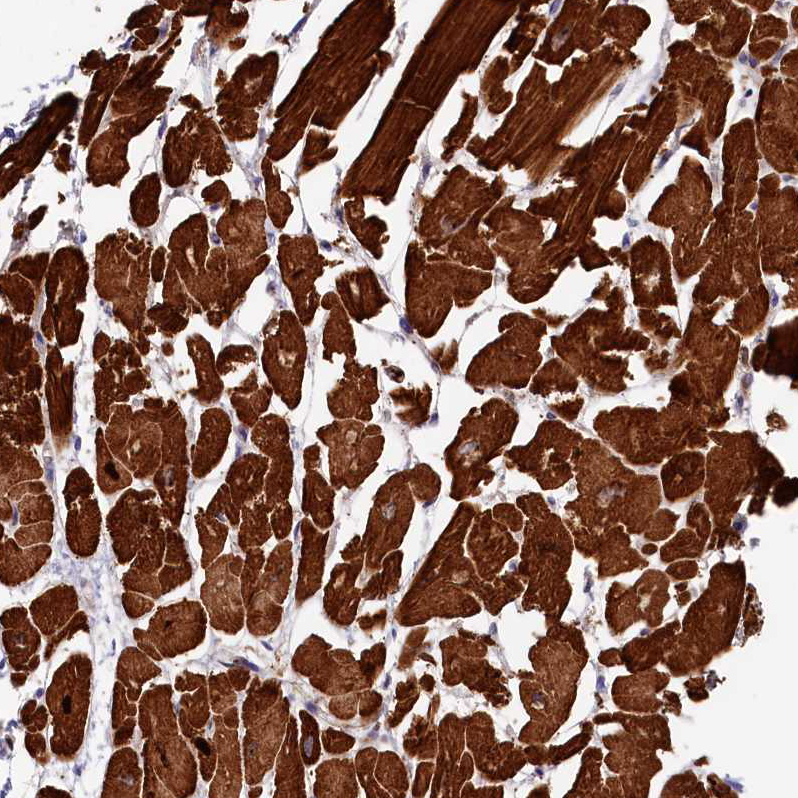

Immunohistochemical staining of human skeletal muscle shows strong cytoplasmic positivity in myocytes.